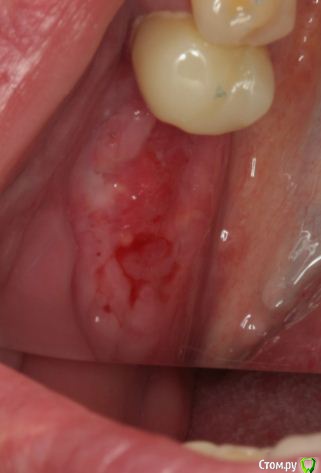

Endorphin Опубликовано 9 сентября, 2015 Автор Поделиться Опубликовано 9 сентября, 2015 (изменено) Продолжение истории.По Вашим советам мембрану оставил, наблюдал пациентку раз в неделю. Отмечалась тенденция к росту области прорезывания, в связи с чем было решено мембрану удалить ( не хотелось дожидаться оголения края мембраны). На момент удаления мембране исполнилось 3 месяца. Анестезия, разрез по гребню примерно на 3/4 длины мембраны. Мембрана и пины ушли без боя, в области прорезывания обнаружился желеобразнный фибрин. Там, где над мембраной сохранилась слизистая, на месте графта образовалась твердая ткань, надо полагать, выросла кость. Иммобилизировать, ушивать наглухо, подкладывать сст не стал. Наложил сближающие швы, швы на разрез. Прошла неделя. Через 1.5 - 2 месяца планирую КТ и если это действительно была кость, то имплантацию с сст. Спасибо всем, кто отговаривал меня удалять мембрану . Изменено 9 сентября, 2015 пользователем Endorphin 13 Ссылка на комментарий

andrey_1965 Опубликовано 29 ноября, 2015 Поделиться Опубликовано 29 ноября, 2015 Продолжение истории.По Вашим советам мембрану оставил, наблюдал пациентку раз в неделю. Отмечалась тенденция к росту области прорезывания, в связи с чем было решено мембрану удалить ( не хотелось дожидаться оголения края мембраны). На момент удаления мембране исполнилось 3 месяца. Анестезия, разрез по гребню примерно на 3/4 длины мембраны. Мембрана и пины ушли без боя, в области прорезывания обнаружился желеобразнный фибрин. Там, где над мембраной сохранилась слизистая, на месте графта образовалась твердая ткань, надо полагать, выросла кость. 3month.JPG 3month2.JPG Иммобилизировать, ушивать наглухо, подкладывать сст не стал. Наложил сближающие швы, швы на разрез. Прошла неделя. epithelium1.JPG epithelium2.JPG Через 1.5 - 2 месяца планирую КТ и если это действительно была кость, то имплантацию с сст. Спасибо всем, кто отговаривал меня удалять мембрану .Пора КТ показать. Ссылка на комментарий

Endorphin Опубликовано 30 января, 2016 Автор Поделиться Опубликовано 30 января, 2016 Сделайте фото когда ставить будете, очень интересноСделал.Результат превзошел ожидания. Из-за изначально неправильного расположения мембраны и графта, "ширина" начинается лишь отступя 6.5 мм от шейки 45, так что центр платформы дистализирован для моляра (8.5мм когда хочется 6мм). Качество фото так себе, но суть, думаю, ясна - кость наросла в достаточном объеме и качестве, торк > 45. Обязательно ССТ под швы. Еще раз всем спасибо! 1 Ссылка на комментарий